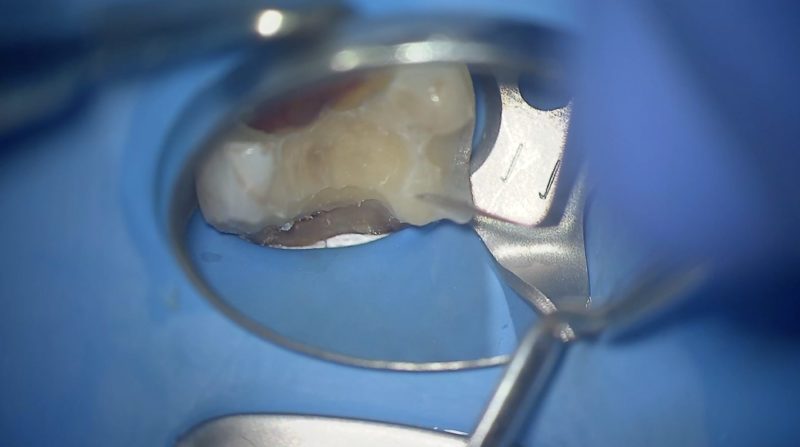

接着阻害因子を排除するために圧排します。

バキュームで吸引しながら湿度管理をして隔壁をたてます。

この時鼻からの呼気がが入らないようにラバーダムで鼻を隠しています。

近心も同様に隔壁をたてます。

続いて頬側ですが、ここはクランプに工夫をしなければなりません。

頬側の隔壁